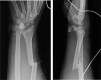

Trans-scaphoid lunate dislocation with volar displacement into the wrist/distal forearm is a devastating injury that most commonly occurs under situations of forceful impact to an extended wrist. Due to ligamentous disruption as well as fragile blood supply, these Mayfield type 4 injuries are associated with significant morbidity and long-term sequelae. Current treatment approaches to lunate dislocations depend on the severity and chronicity of the injury in addition to patient factors, with operative management potentially including ORIF or proximal row carpectomy. We report 5 cases of this rare injury pattern in 4 different patients.